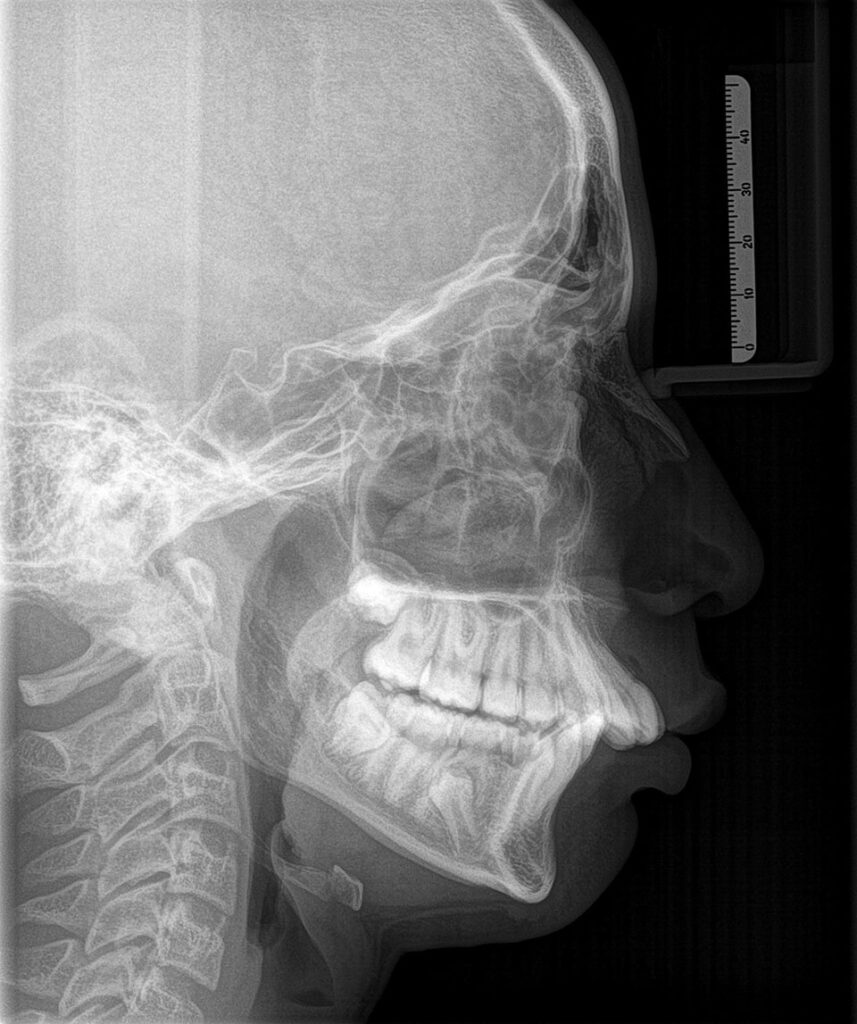

We use both intraoral and extraoral digital imaging depending on your needs:

- Extraoral: Panoramic or full-jaw shots as needed

- Planning implants, root canals, or extractions

- Tracking structural changes over time